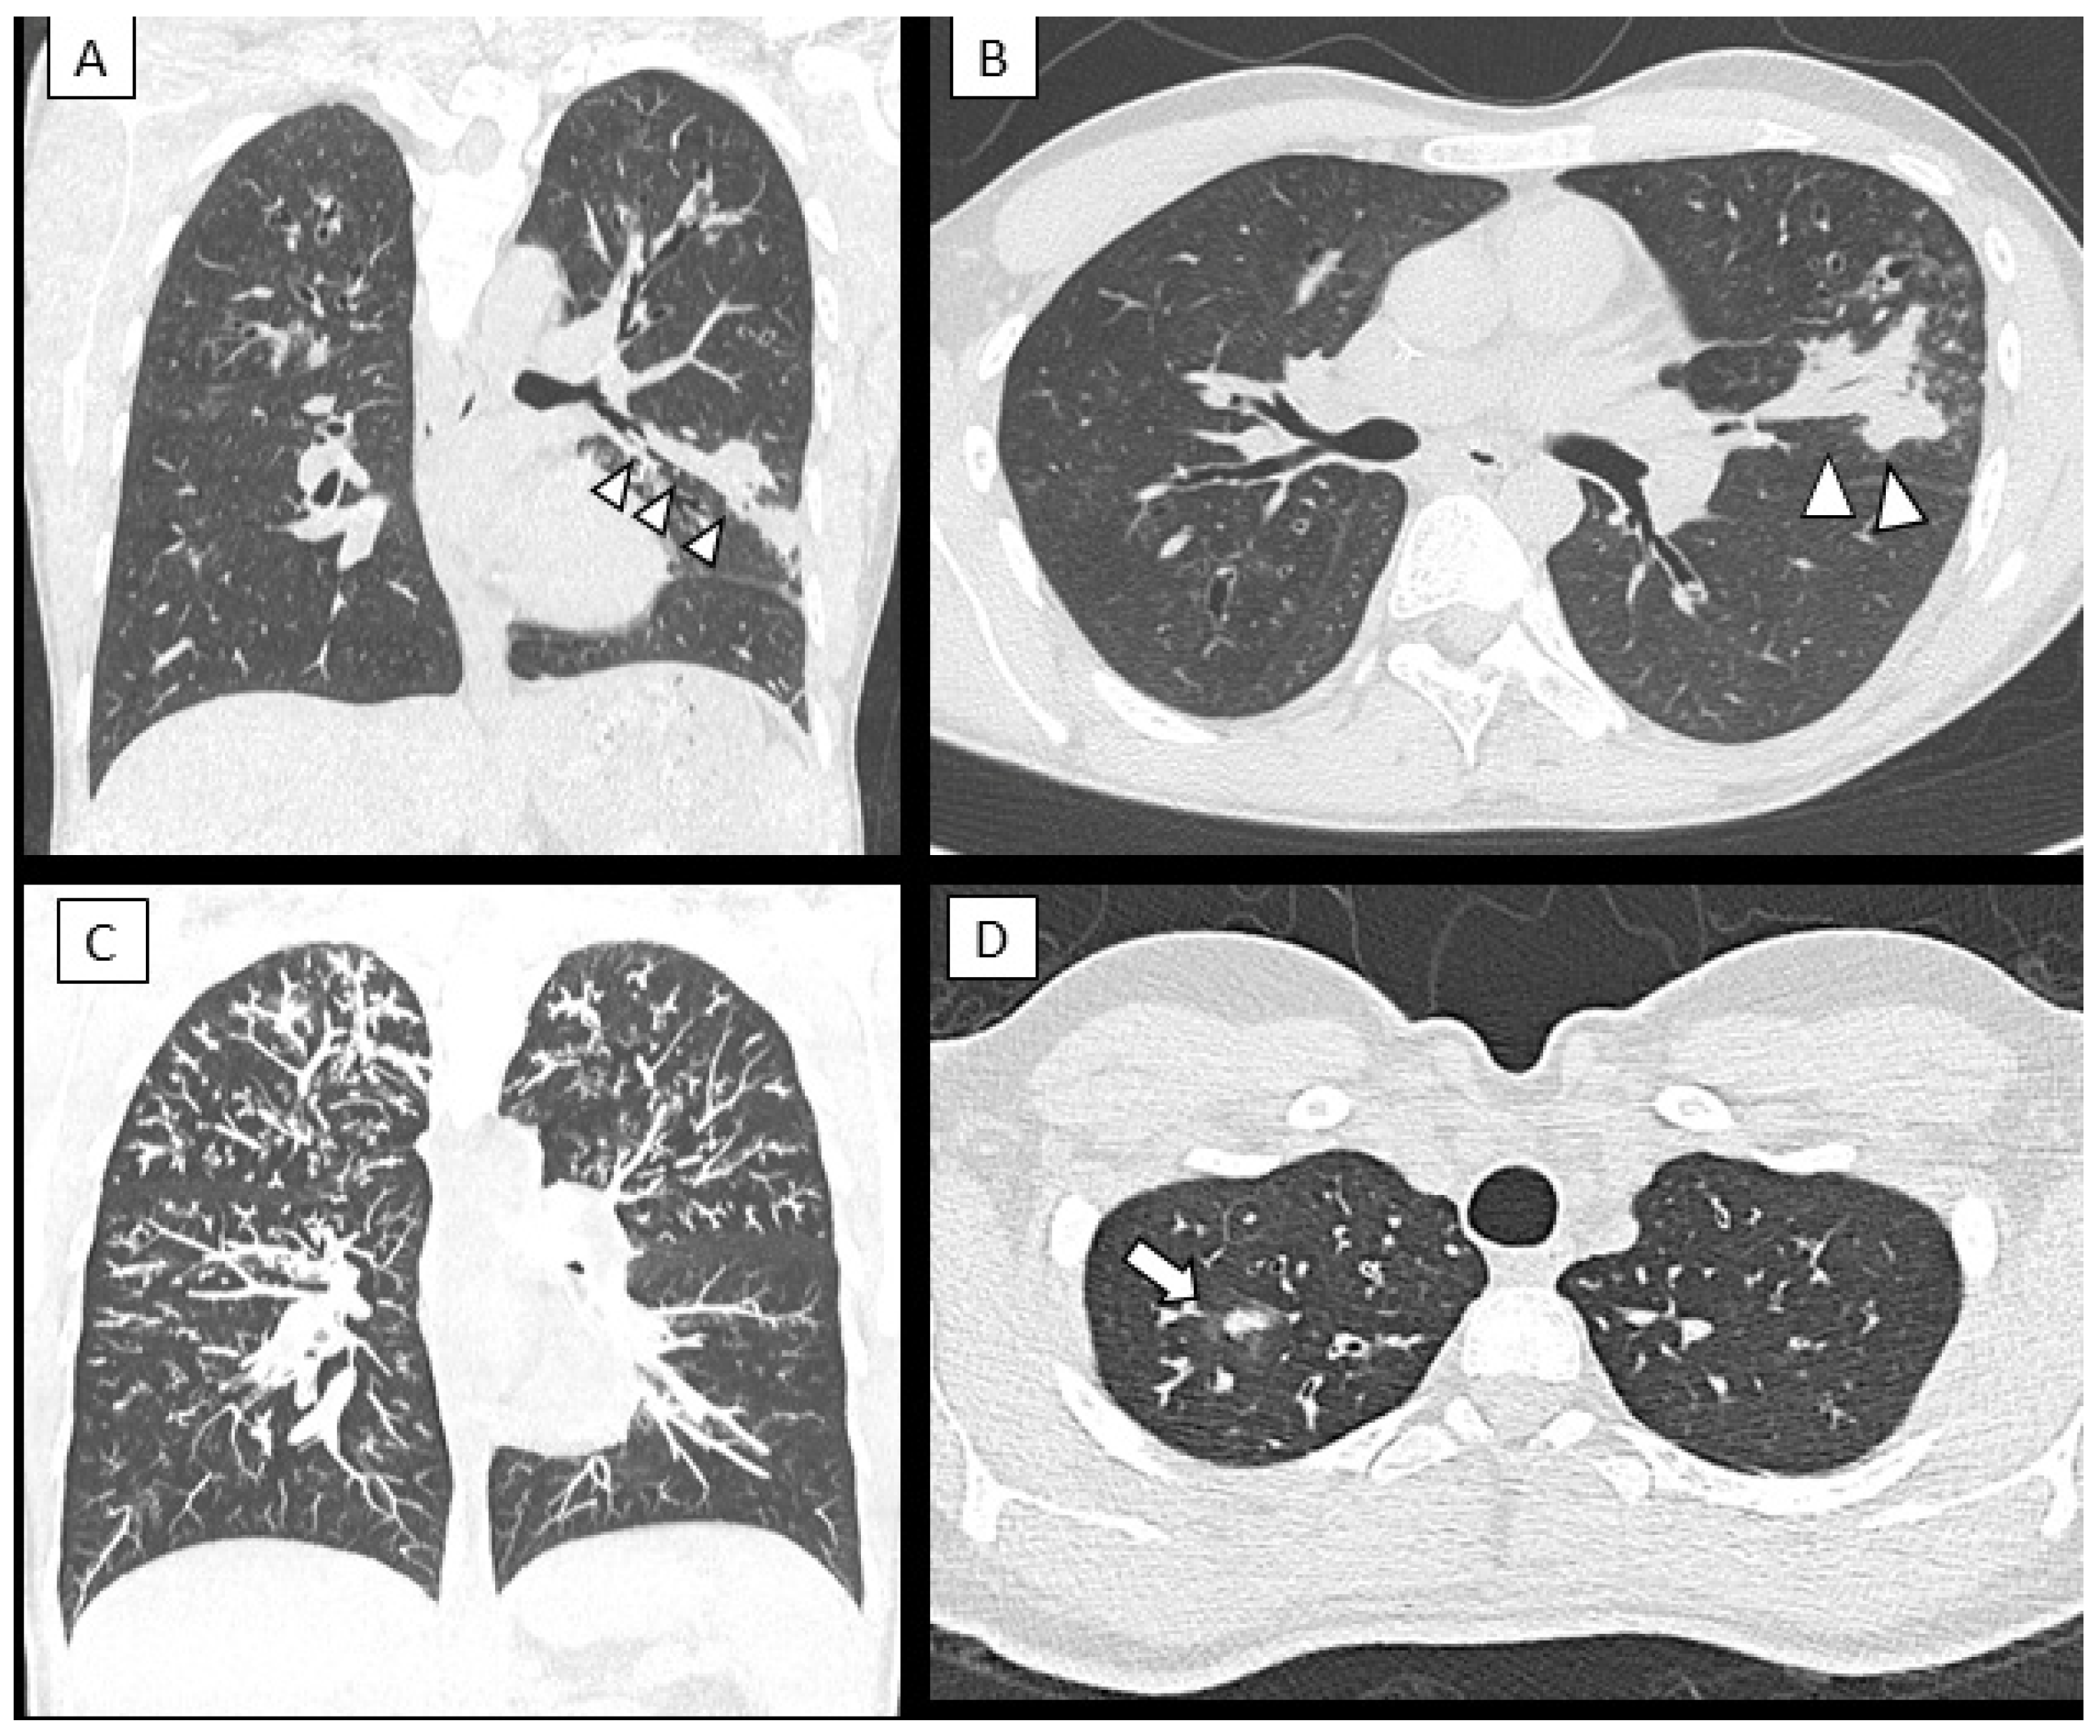

- Lv, Q.; Elders, B.B.L.J.; Warris, A.; Caudri, D.; Ciet, P.; Tiddens, H.A.W.M. Aspergillus-related lung disease in people with cystic fibrosis: Can imaging help us to diagnose disease? Eur. Respir. Rev. 2021, 30, 210103. [Google Scholar] [CrossRef]